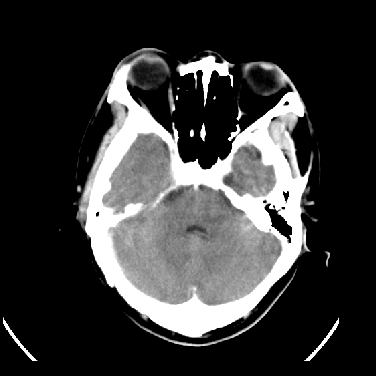

男,45岁,左侧肢体乏力1周。ex:胸片示:两肺团块状、斑片状密度增高影,其内可见小空洞。支纤镜、经皮肺穿示:干酪样物。

结合病史考虑结核性脑炎脑膜炎,伴脑脓肿形成

考虑右侧顶叶脑脓肿形成。

同意“考虑结核性脑炎脑膜炎,伴脑脓肿形成”的意见,不轻易怀疑肿瘤。

考虑结核性脑炎脑膜炎,伴脑脓肿形成。

考虑右侧顶叶脑脓肿(结核性?)。

结核性脑脓肿可能大

结合病史考虑结核性脑炎脑膜炎,伴脑脓肿形成,囊变转移瘤不除外